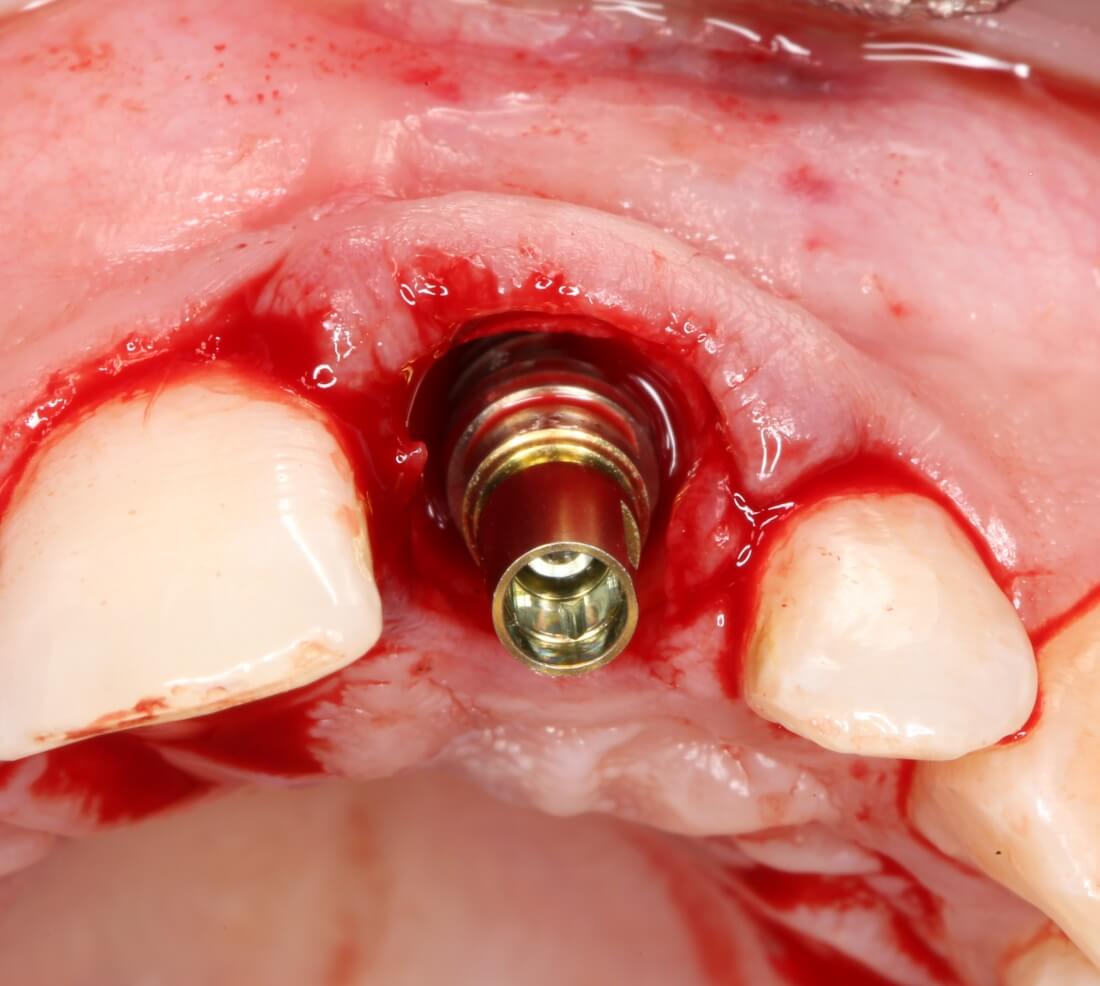

Установка имплантатов

По ряду уже упомянутых выше причин, для решения этой клинической задачи мы выбрали имплантаты Xive. Лунки для них мы уже приготовили. возможную первичную стабильность оценили. Имплантаты мы установили с усилием чуть больше 15-20 Нсм — такого крутящего момента более, чем достаточно, особенно если учесть, что временные коронки будут соединяться между собой.

Подробно о том, что такое крутящий момент и хирургический протокол можно прочитать здесь>> и тут>>, соответственно. Из-за использования специальных индивидуализируемых временных абатментов, имеющих только три положения, нам нужно позиционировать платформу имплантатов по граням. Это очень просто  — мы выводим вырез абатмента TempBase (он входит в комплект поставки) вестибулярно.

После перкуторной проверки стабильности имплантатов и точности позиционирования, мы переходим к следующему этапу — сохранению десневого контура.

Установка имплантатов занимает около двух минут.